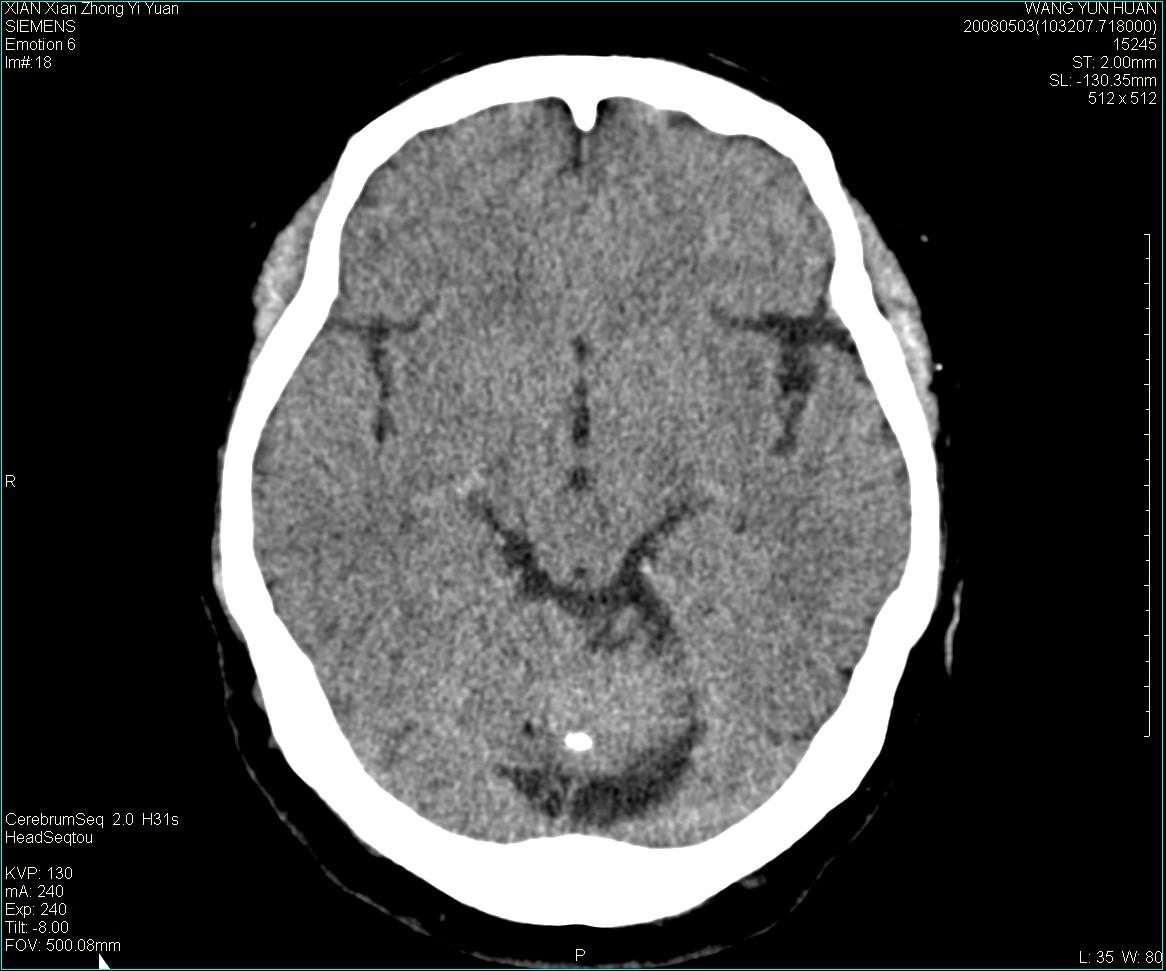

标题: CT13219:(补充强化)请会诊,患者女,60岁,头晕,大家看 [打印本页]

标题: CT13219:(补充强化)请会诊,患者女,60岁,头晕,大家看

病灶显示轻度强化,ct增加4hu左右,大家看是什么肿瘤.

强化后动脉期及延迟2分钟,五分钟图像

小脑蚓部囊型肿块,内有实性结节及钙化点。增强后囊壁及结节轻度强化。

考虑蚓部星形细胞瘤(ⅱ级可能性大)。

小脑蚓部肿块,周围无明显占位效应及水肿带,增强轻度强化,考虑低分级星形细胞瘤。